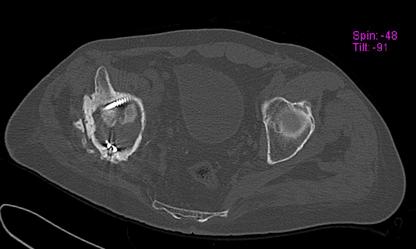

Пациент 49 лет, паровозная травма 23.2.2006, получил вертикальная нестабильное повреждение таза, разрыв левого крестцово-подвздошного сочленения, перелом лонной, седалищной костей слева, T-образный оскольчатый перелом правой вертлужной впадины с переломом заднего края, вывих правого бедра, посттравматическая пояснично-крестцовая плексопатия с обеих сторон, паралич мышц правой голени.

В день травмы - вправление вывиха, скелетное вытяжение, 14.3.2006 чрескостный остеосинтез таза. 20.4.2006 остеосинтез правой вертлужной впадины пластинами, осложнившийся нагноением межмышечной гематомы правой ягодичной области. Получал консервативное лечение, было достигнуто полное заживление раны. 24.7.2006 введены илиосакральные винты слева. С декабря 2006 года и по настоящее время ходит на костылях без опоры на правую ногу. Планируется THA. Помогите определиться с вариантом костной пластики? И какую укрепляющую конструкцию использовать?